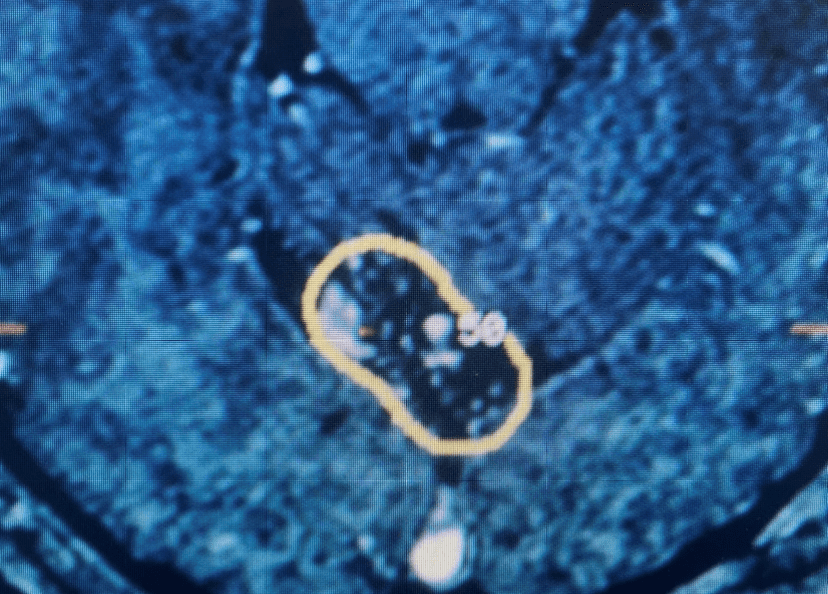

Grade II Oligodendroglioma

Author: Ramin Rak M.D., F.A.A.N.S., F.C.N.S., Read More!

Brain:

Pituitary Tumor with Cushing’s Disease

Author: Michael Brisman M.D., F.A.C.S., Read More!